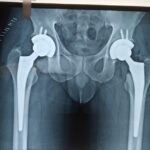

Hip replacements consist of multiple parts – the acetabular shell or socket is made of titanium which accommodates an inner insert made of highly cross-linked polyethylene. On the femoral side, the stem is made of titanium and can accommodate different sized ceramic heads. There is no metal on metal components as existed in previous designs.

We have been able to make significant improvements in the components that we use during hip replacement surgery. The benefit has been increased stability and lower wear rates of the inserts with the use of highly cross-linked polyethylene. Consequently, the issues with “wearing out” the hip implants are no longer a significant or meaningful concern.